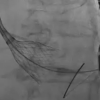

May 20, 2016 — Using optimal frequency domain imaging (OFDI) to guide percutaneous coronary intervention (PCI) with…